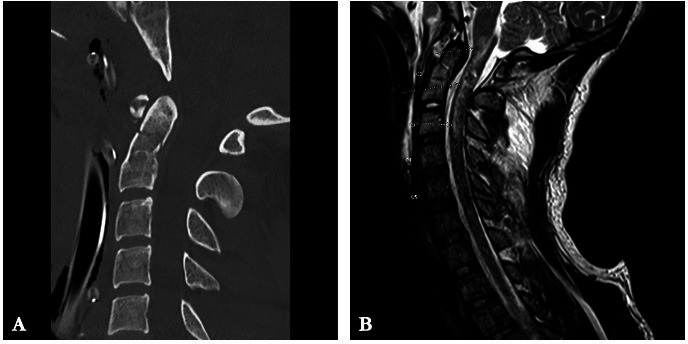

Abstract Image